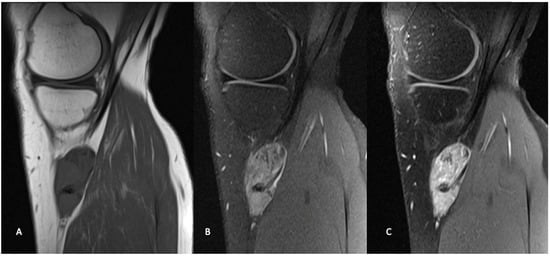

Similar to other STS, magnetic resonance imaging (MRI) with and without contrast is the gold standard for diagnostic imaging for synovial sarcoma (Figure 2) []. MRI defines the local extent of the soft tissue mass and surrounding edema and provides excellent visualization of the mass with respect to the surrounding anatomy, which is critical for preoperative planning. The utilization of gadolinium contrast can differentiate between hemorrhagic or necrotic areas and areas of solid viable tumor. As with most STS, synovial sarcomas are typically heterogenous with low intensity on T1 and high intensity on T2-weighted images with post-gadolinium enhancement [].

Figure 2.

Sagittal MR images in the same patient demonstrate a periarticular soft tissue mass situated posteromedial to the proximal tibia, in close relation to the pes anserine tendons. The mass demonstrates intermediate signal on T1 weighted images (A), and heterogeneously high signal on T2 weighted fat-saturated images (B). T1 weighted fat-saturated after gadolinium administration (C), demonstrates heterogeneously avid enhancement. Known areas of calcification are low signal on all sequences (arrow).

Although synovial sarcomas generally present as a non-specific heterogenous mass, there are some unique features, which can aid in differentiation from other STS. Synovial sarcomas predominately present as well-defined, heterogeneously enhancing solid tumors that are multilobulated in nature []. A triple signal intensity demonstrating areas of hyperintensity, isointensity and hypointensity indicating the mix of cystic and hemorrhagic areas, cellular elements and fibrotic areas can be characteristic []. Smaller tumors, particularly those smaller than 5 cm in diameter, often show homogeneous enhancement which can be mistaken for a benign process []. Several findings on MRI have been found to be predictive of high-grade lesions including the absence of calcifications and presence of hemorrhage and the triple signal intensity [].